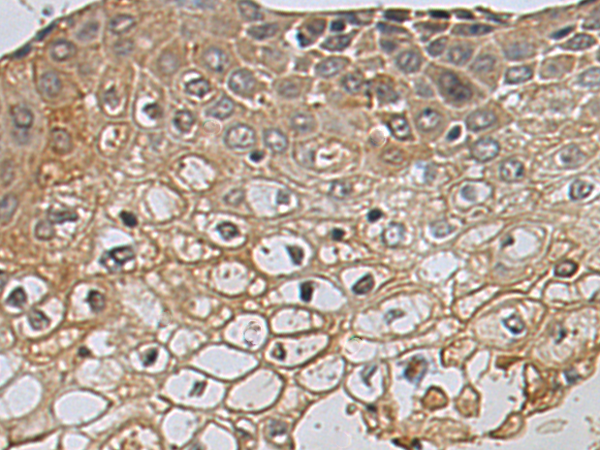

分类: 科研抗体货号: P05755别名: E2F-8应用: WB,IHC反应种属: Human, Rat